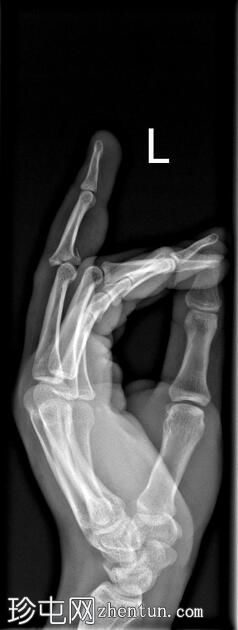

左

手外

伤。

X线片

侧位

可见第三指中节指骨基底部轻微移位骨折,延伸至近端指间关节(PIP关节),并伴有软组织肿胀。

第三指中节指骨基底部轻微移位骨折,延伸至近端指间关节(PIP关节)指骨,并伴有软组织肿胀。